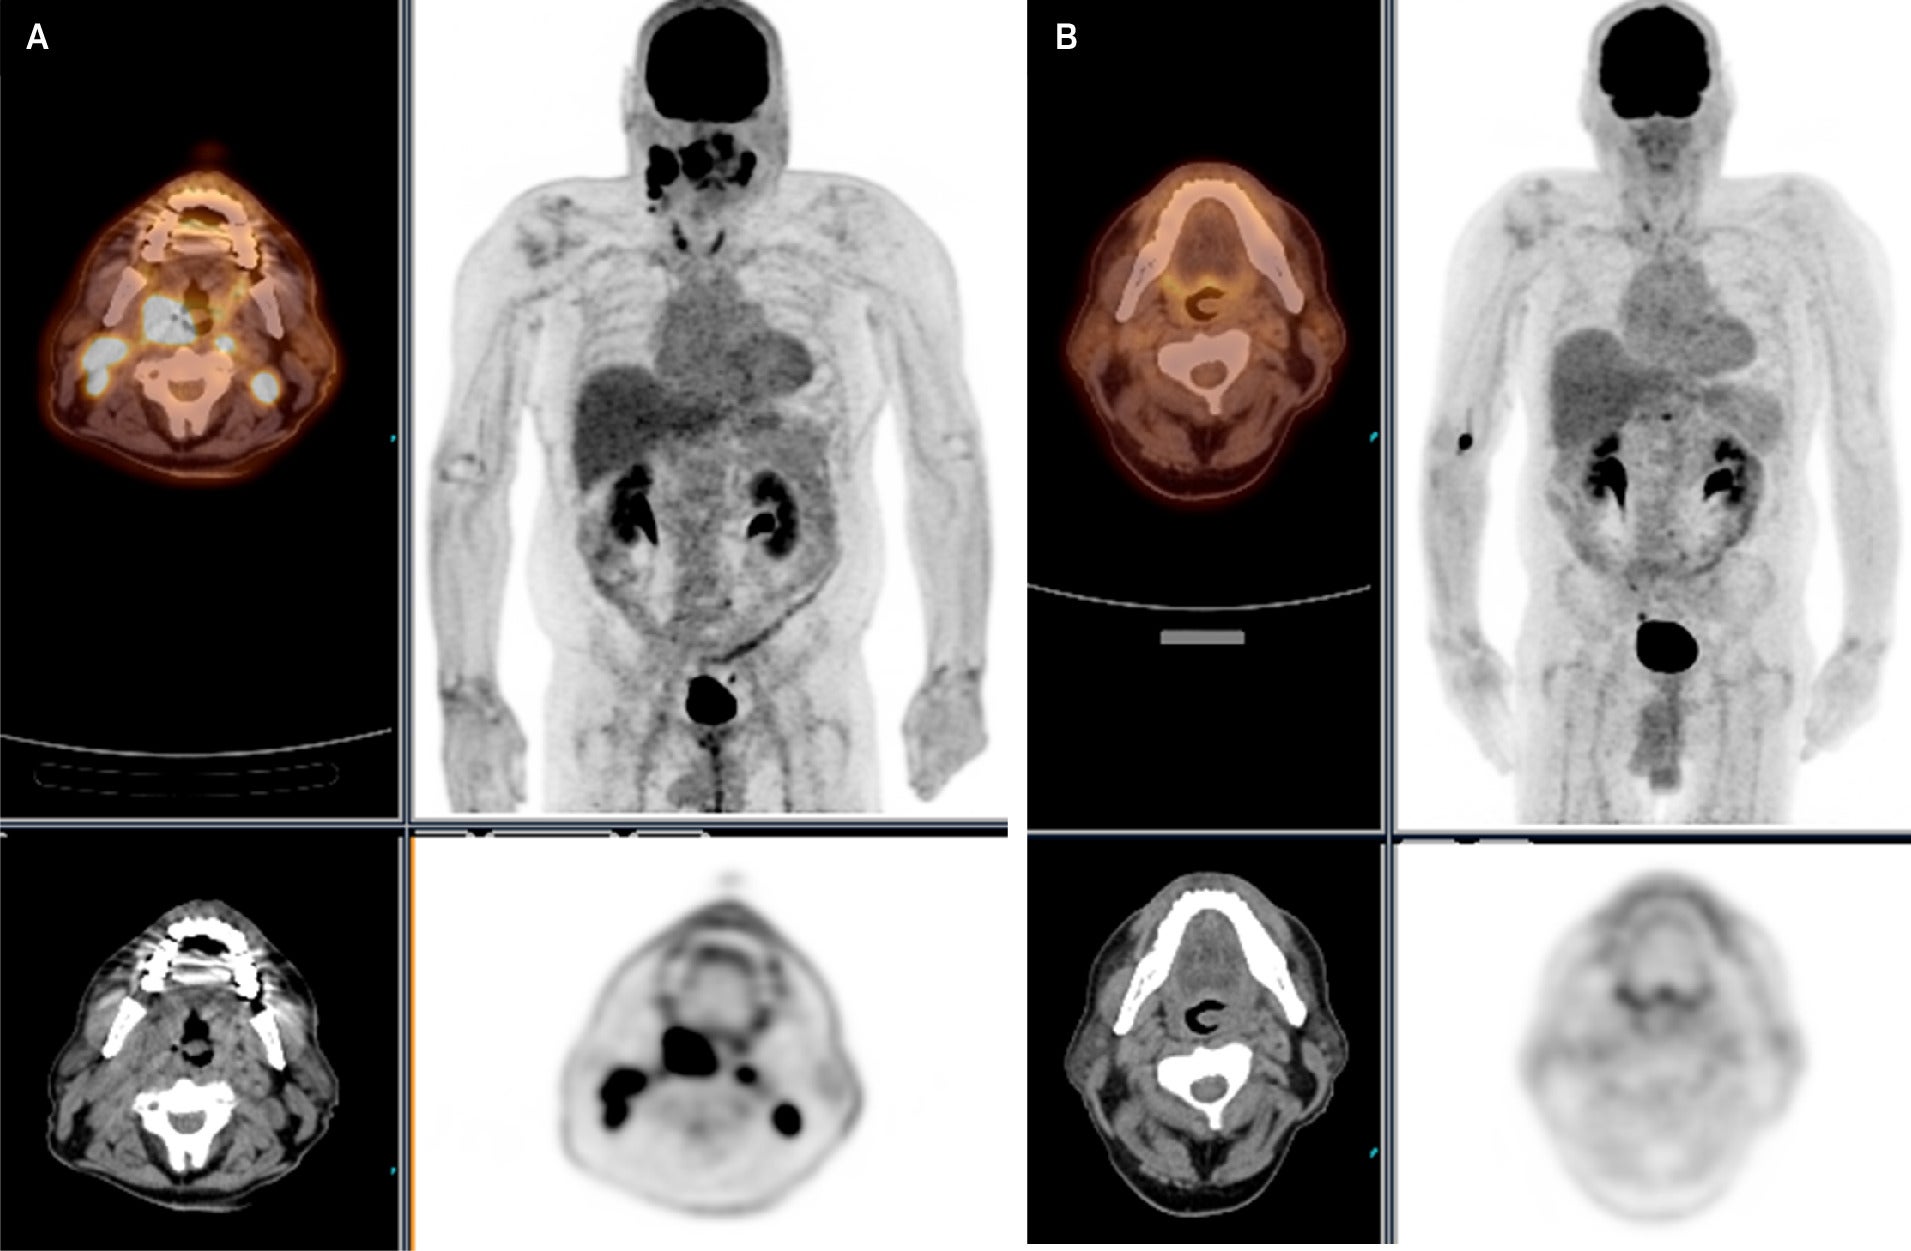

Pulmonary Artery Pseudoaneurysm